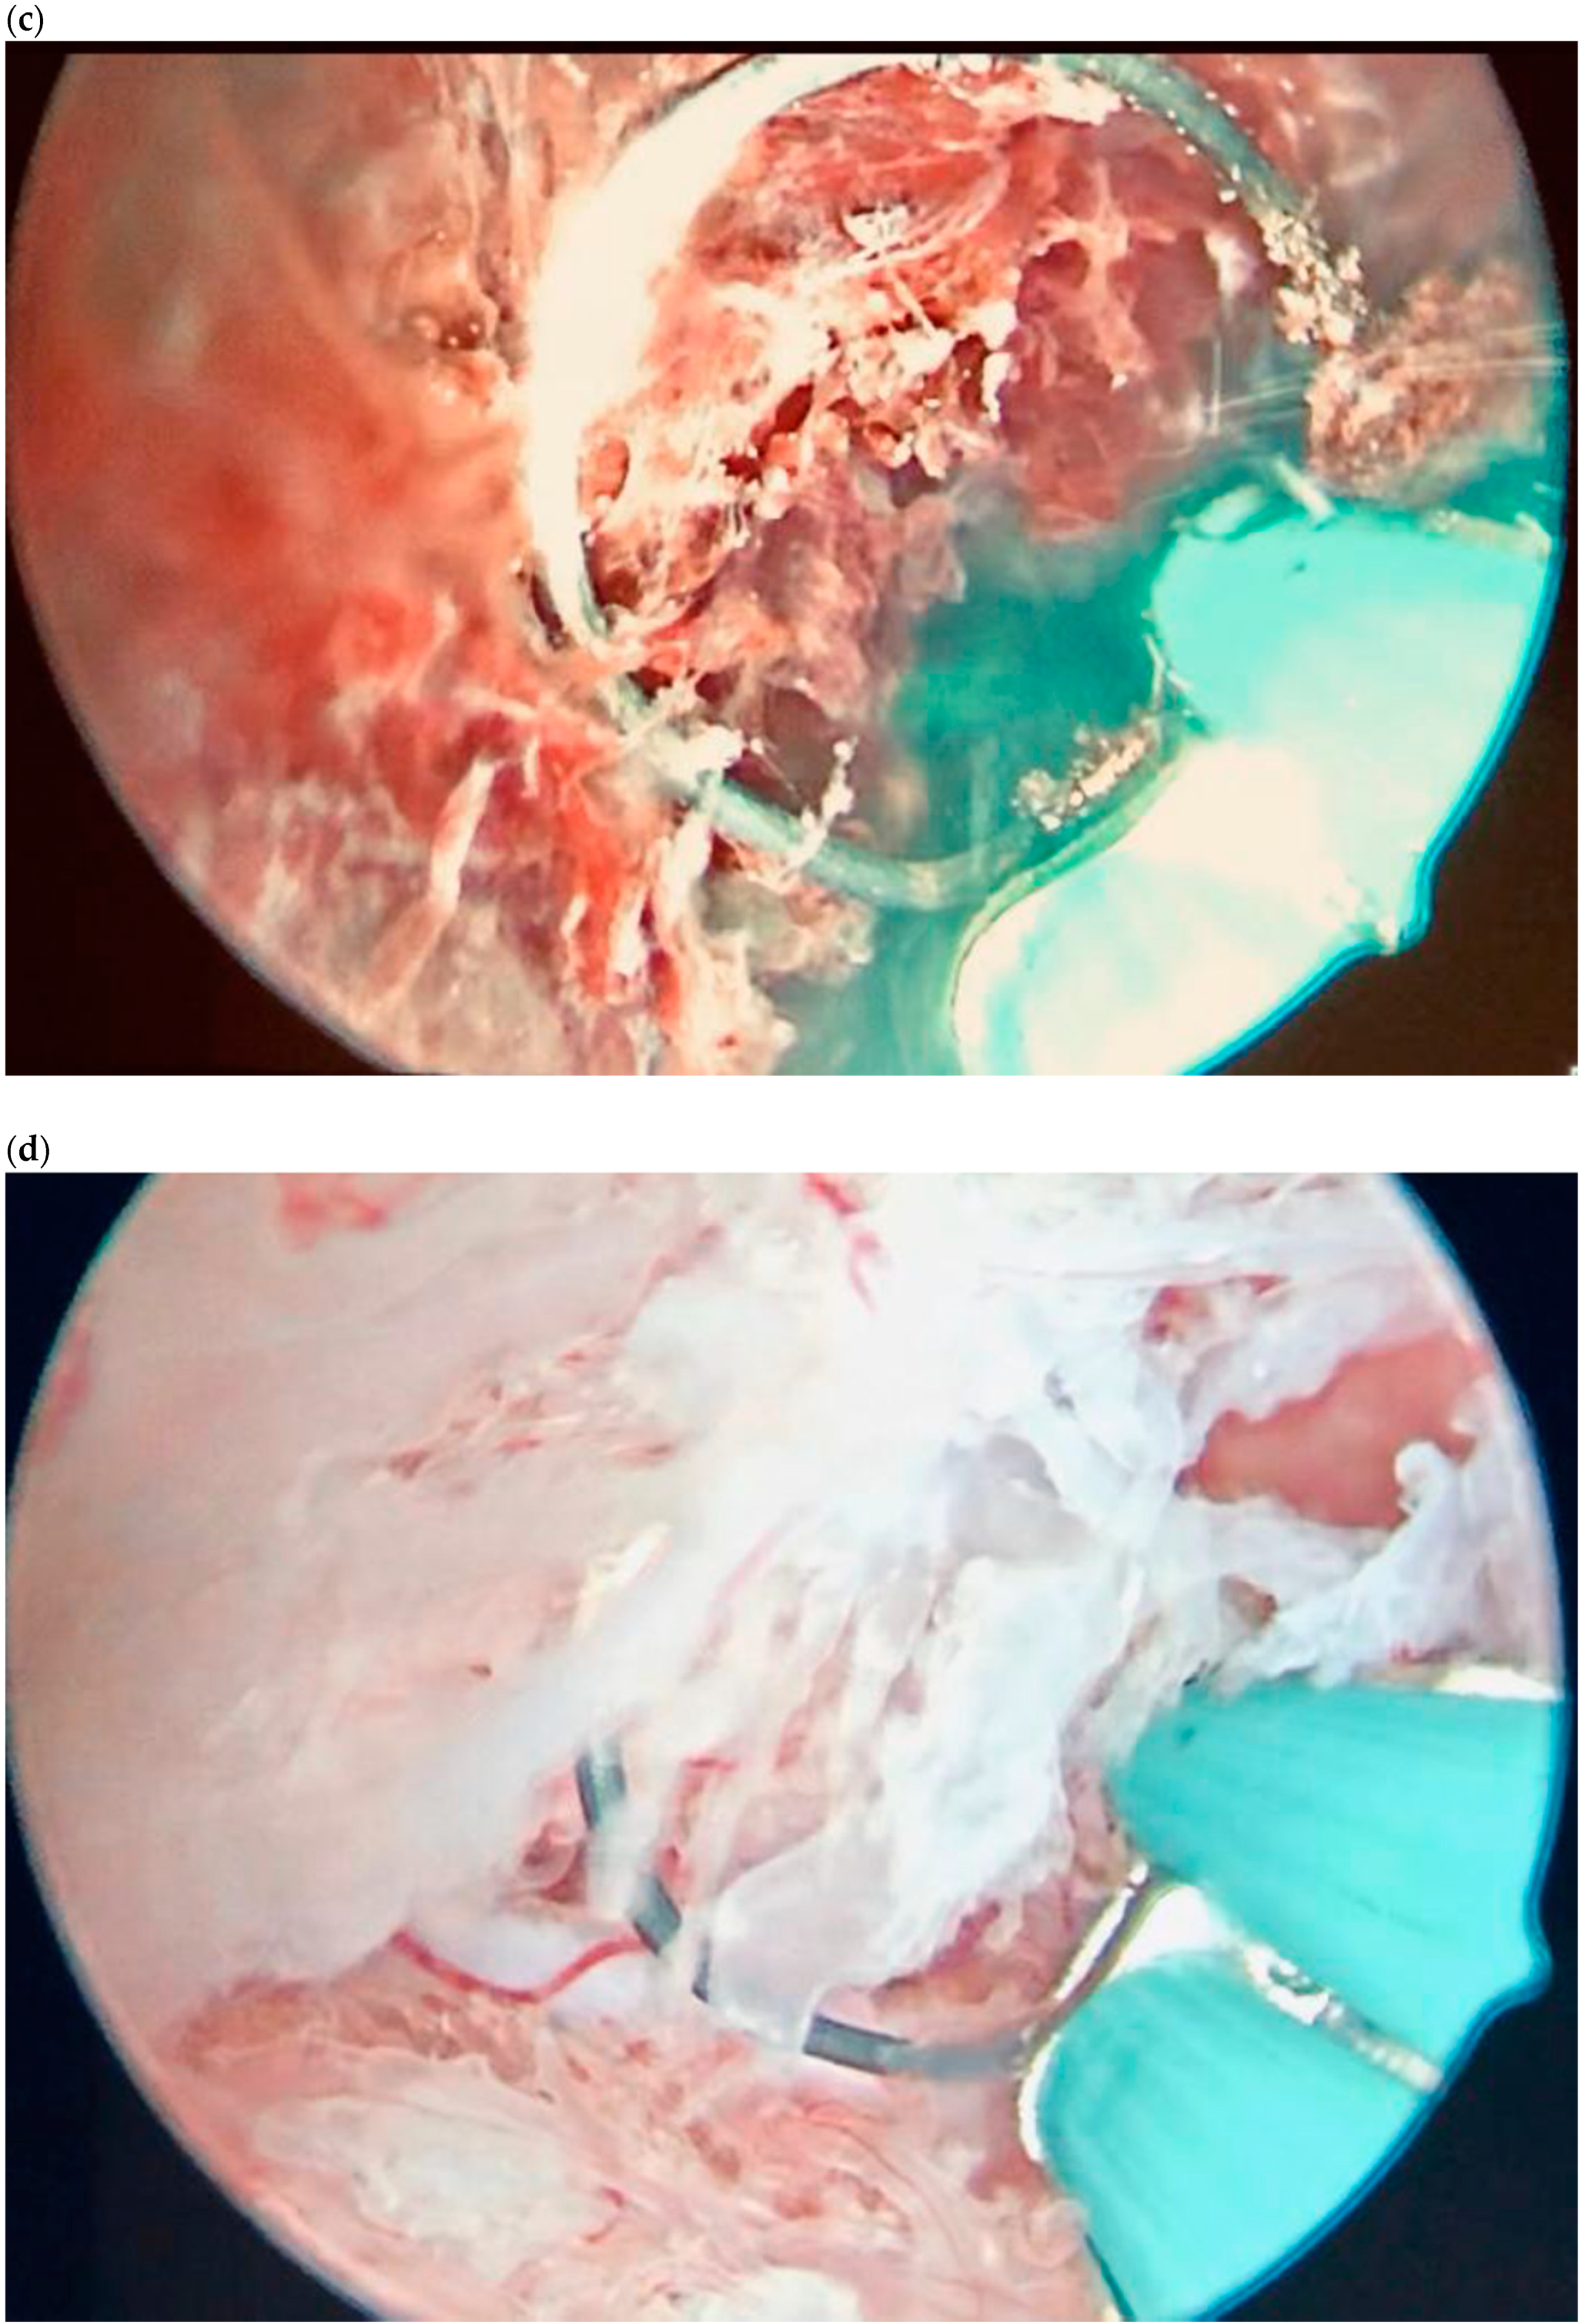

| Case 1 | Asymptomatic | 6 | 119,900 | GS 14 × 16 mm | MTX IM 50 mg/m2 of body surface + Misoprostol 200 µg rectal + Hys (two times) + Curettage | Complete resolution |

| Case 2 | Asymptomatic | 6 + 2 | 31,647 | GS 12 × 10 mm | Mifepristone 600 mg + Misoprostol 400 mcg + Hys: reseptoscopy | Complete resolution |

| Case 3 | Asymptomatic | 7 + 1 | 131,000 | GS 9 × 10 mm | Hys: twizzle and minireseptor + Curettage  | Complete resolution |